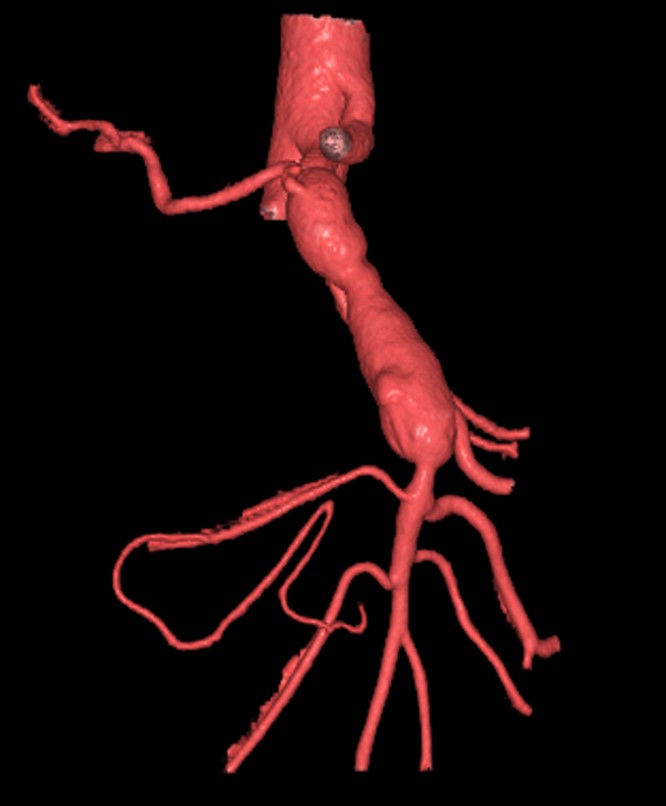

NF-1参考症例 53歳男性

• 偶然発見

• 腹腔動脈とSMAの狭窄